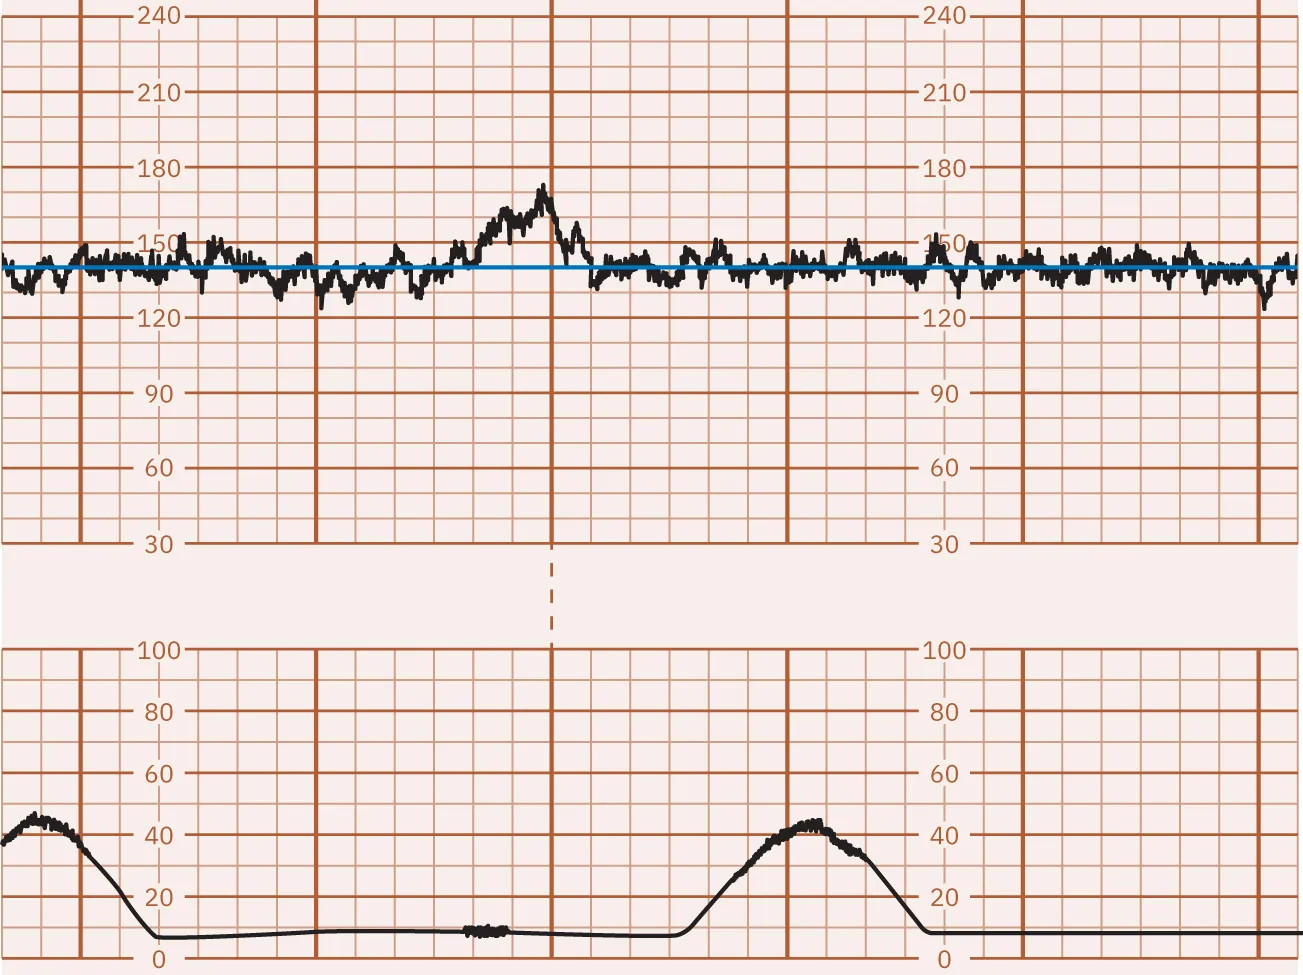

Late Decelerations

Decelerations in the FHR below the baseline that start during a contraction and continue after completion of the contraction are called late decelerations. Figure 16.12 illustrates late FHR decelerations. Late decelerations are nonreassuring and almost always indicate fetal hypoxia. They are associated with uteroplacental insufficiency, a lack of oxygenated blood coming from the uterus to the placenta to the fetus. During a contraction, the decrease in oxygen to the fetus causes a deceleration that begins late in the contraction. The nadir, or lowest point, of the deceleration is after the peak of the contraction. Another common cause of late decelerations is tachysystole (contractions occurring too frequently or lasting longer than 2 minutes), often seen with the use of oxytocin (Pitocin). Spinal or epidural anesthesia causes hypotension leading to hypoperfusion to the placenta, producing late decelerations. Other causes of late decelerations are hypertension, postmature placenta, placental abruption, and anemia. Late decelerations, like early decelerations, are often repetitive, forming a pattern.

Fetal heart rate reading indicating late decelerations.

Figure 16.12 Monitor Tracing Showing Late Decelerations of the FHR The FHR decreases during the contraction and does not return to baseline until after the contraction ends. These are defined as late decelerations. (attribution: Copyright Rice University, OpenStax, under CC BY 4.0 license)